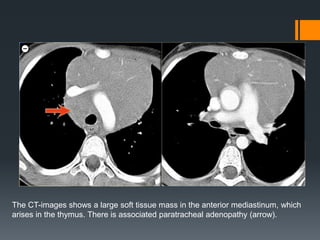

The CT-images shows a large soft tissue mass in the anterior mediastinum, which

arises in the thymus. There is associated paratracheal adenopathy (arrow).